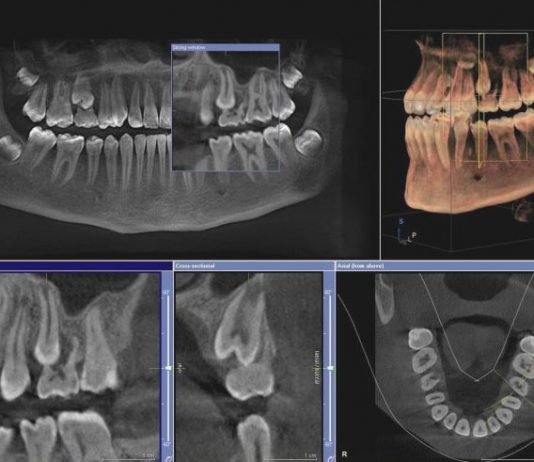

С приходом компьютерной эры появились новые технологии, позволяющие осуществлять мониторинг, диагностику и лечение стоматологических проблем быстрее, проще и тщательнее.

Сегодня трехмерная конусно-лучевая компьютерная томография (КЛКТ) является одним из таких достижений, ставших доступными для клинических стоматологов за последнее десятилетие. Более подробная информация об процедуре и что представляет томография на сайте https://томографиявл.рф.